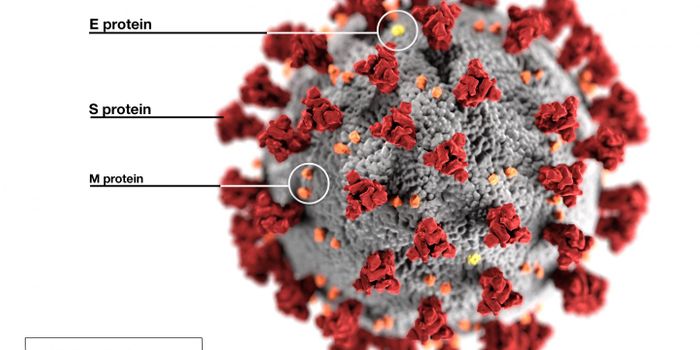

NOV 01, 2021Cell & Molecular BiologyResearchers have learned a lot about the SARS-CoV-2 virus since the start of the COVID-19 pandemic. We know that he viru ...